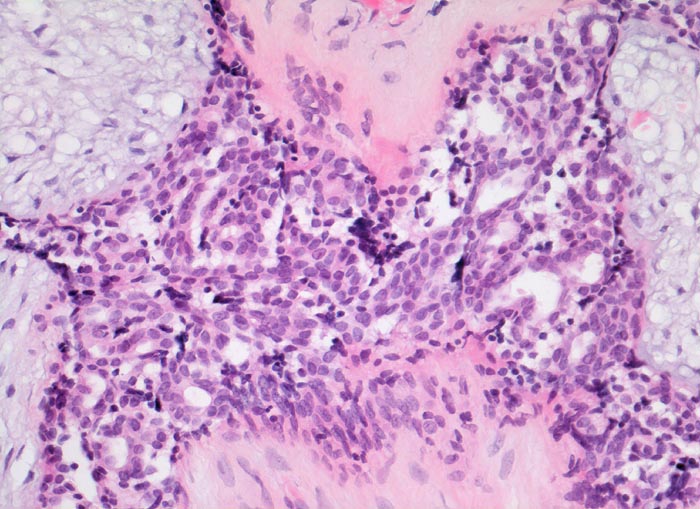

Morphologische Merkmale:

• Zwei scharf begrenzte Tumorknoten.

• Biphasischer organoid aufgebauter Tumor bestehend aus kompaktem zellarmem fibroblastärem Stroma, das in konzentrischen Lamellen um verzweigte, miteinander anastomosierende Drüsenschläuche angeordnet ist.

• Die Drüsenschläuche werden durch das Stroma komprimiert.

• Das Stroma erscheint herdförmig bläulich und aufgelockert durch Muzineinlagerungen.

• Stellenweise gewöhnliche intraduktale Epithelproliferation ohne Atypie.

• Die Drüsen werden ausgekleidet von einer inneren kubischen bis hochprismatischen Zellschicht und einer äusseren abgeflachten Myoepithelschicht mit klarem Zytoplasma.